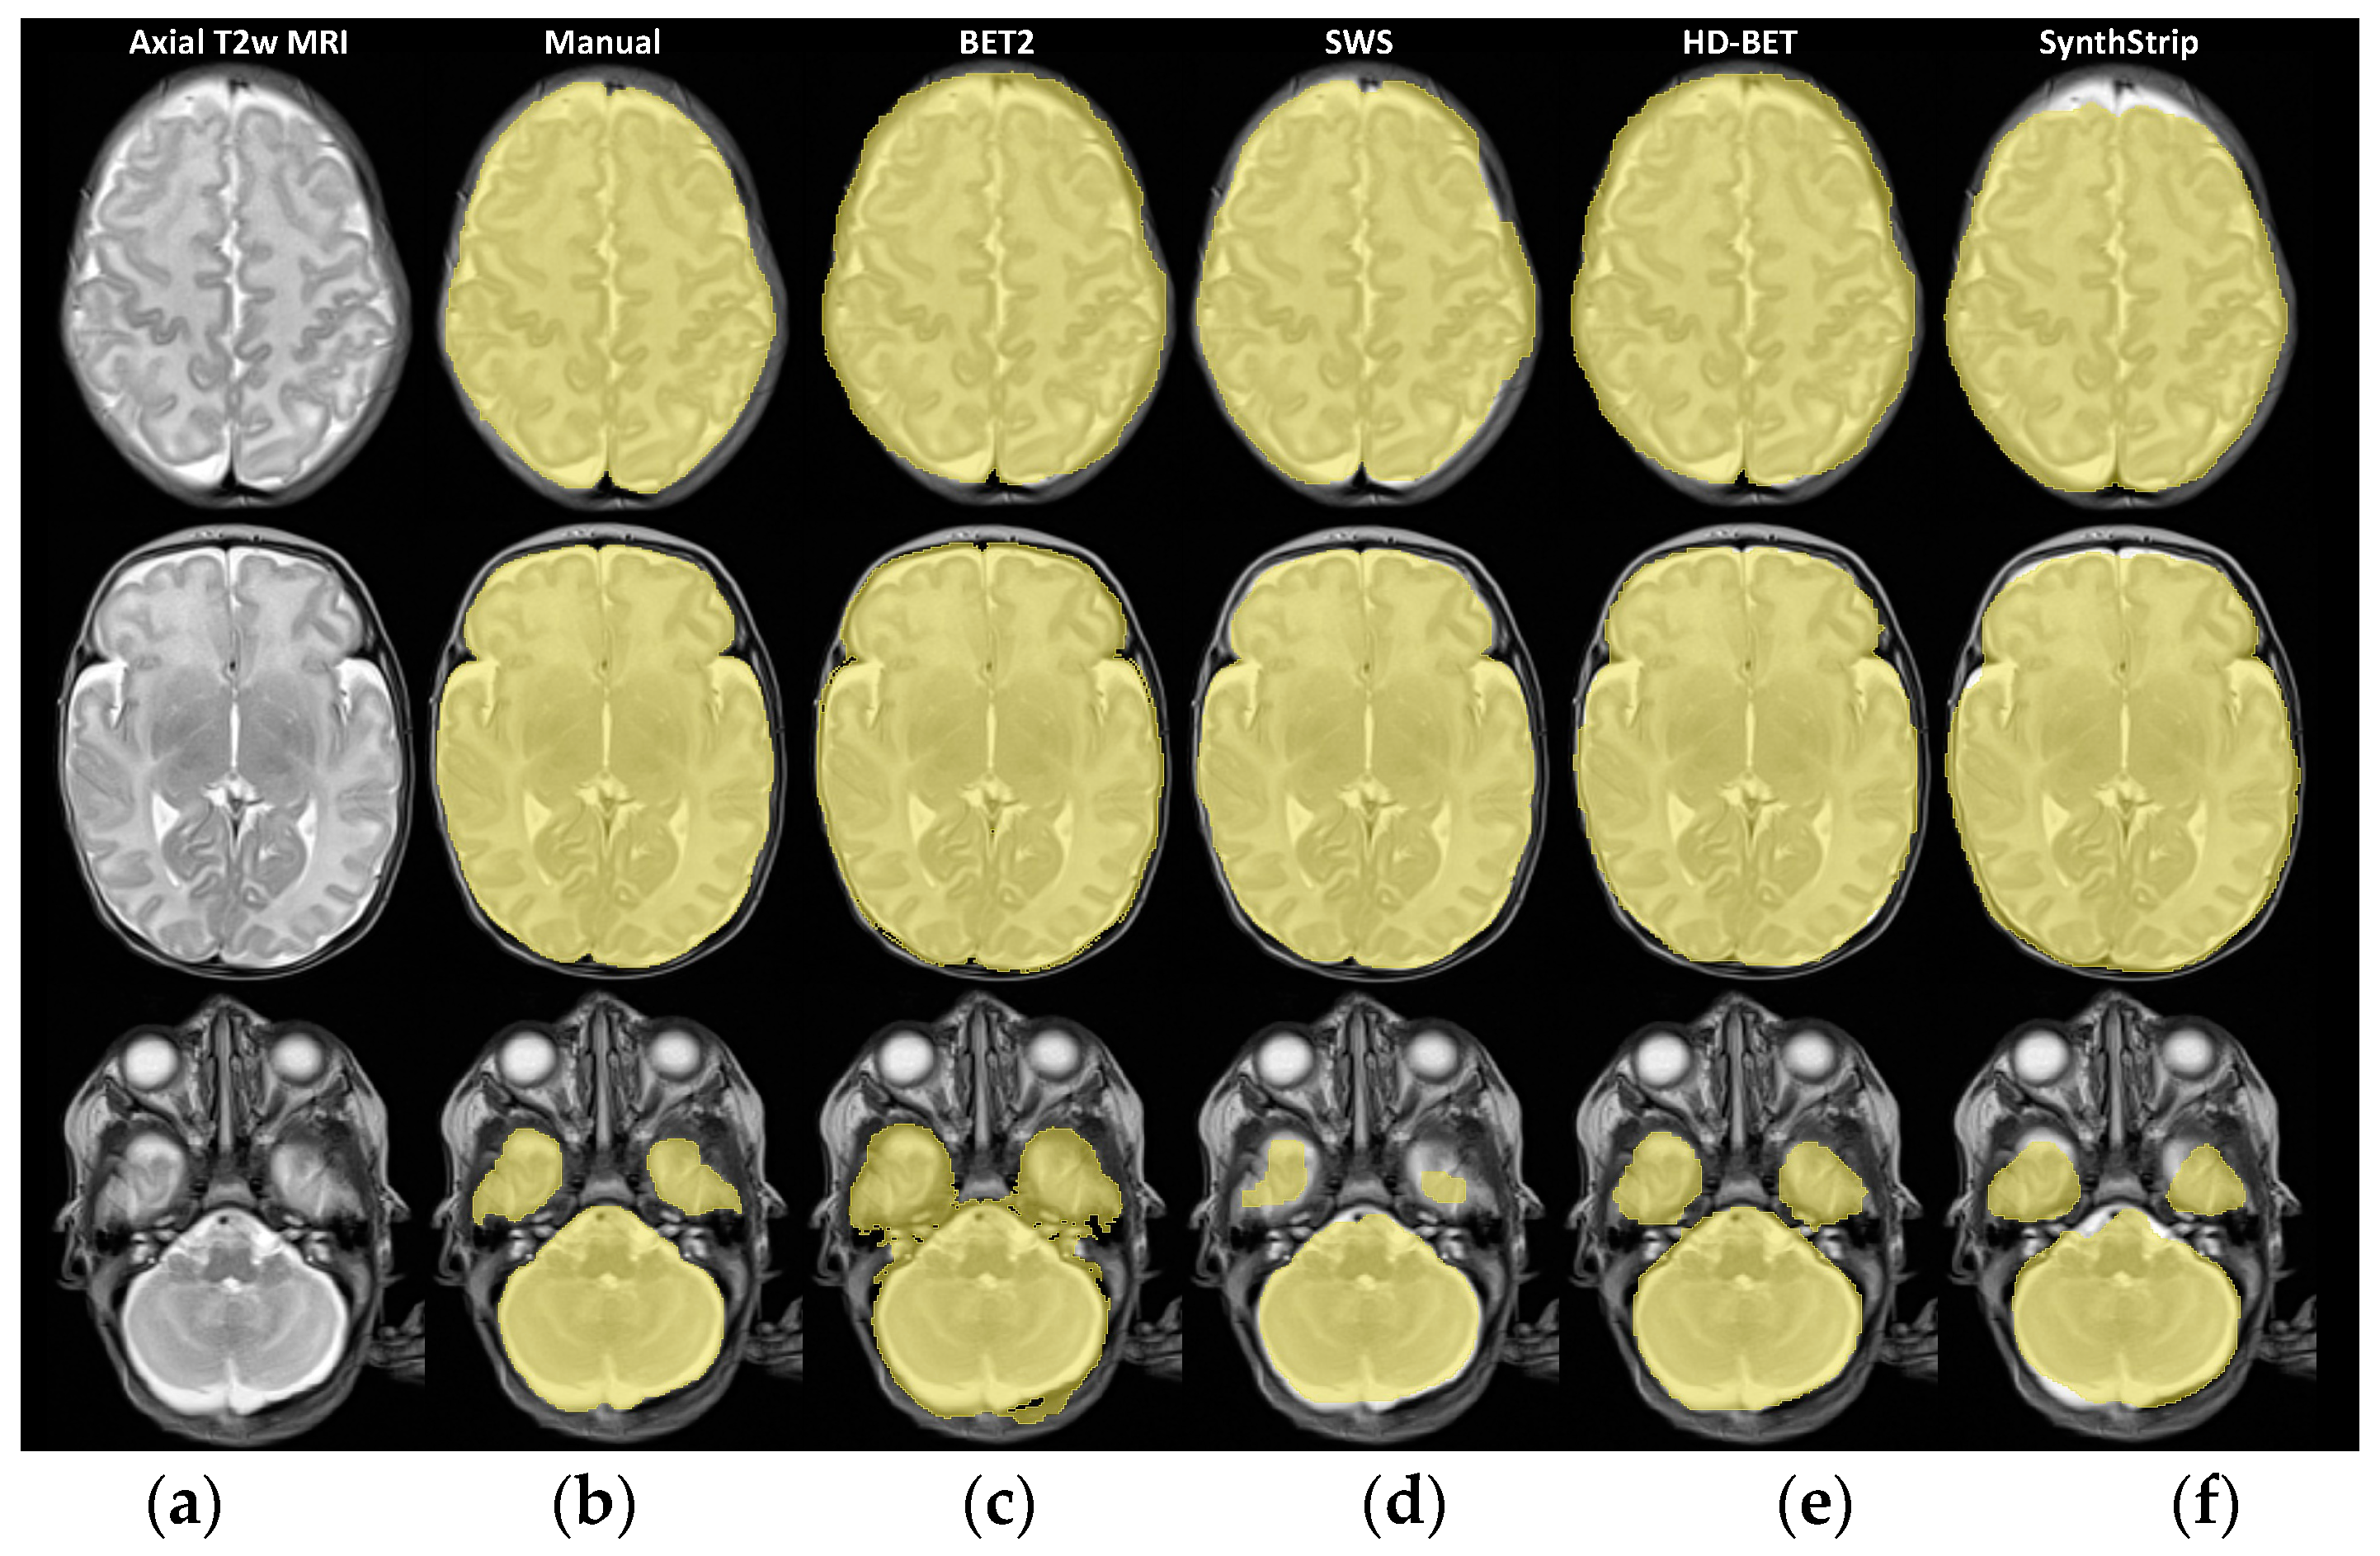

| Median [IQR] of Dice Coefficient | |||

|---|---|---|---|

| Bottom Mask (Slices 1 to 11) | Middle Mask (Slices 12 to 22) | Top Mask (Slices 23 to 33) | |

| BET2 | 0.874 [0.857; 0.883] | 0.961 [0.959; 0.963] | 0.915 [0.904; 0.921] |

| SWS | 0.897 [0.877; 0.905] | 0.983 [0.980; 0.985] | 0.960 [0.947; 0.961] |

| HD-BET | 0.944 [0.935; 0.947] | 0.979 [0.976; 0.980] | 0.962 [0.949; 0.961] |

| SynthStrip | 0.926 [0.913; 0.930] | 0.968 [0.966; 0.970] | 0.948 [0.937; 0.952] |